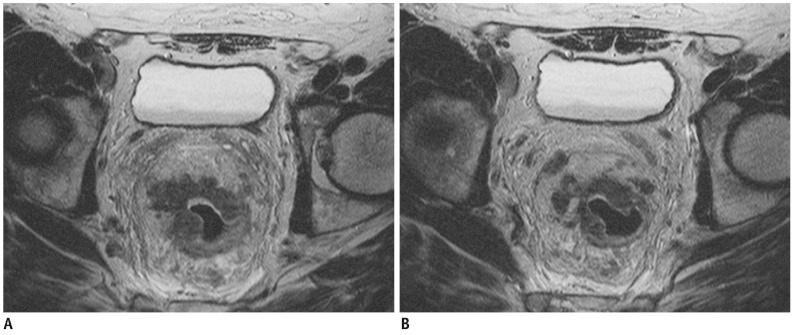

Seventy-three patients with primary rectal cancer underwent high-resolution MRI with a phased-array coil performed using 60-80 mL room air rectal distention, 1-3 weeks before surgery. MRI results were compared to postoperative histopathological findings. The overall MRI T staging accuracy was calculated. CRM involvement prediction and the N staging, the accuracy, sensitivity, specificity, positive predictive value (PPV) and negative predictive value (NPV) were assessed for each T stage. The agreement between MRI and histological results was assessed using weighted-kappa statistics.

The overall MRI accuracy for T staging was 93.6% (k = 0.85). The accuracy, sensitivity, specificity, PPV and NPV for each T stage were as follows: 91.8%, 86.2%, 95.5%, 92.6% and 91.3% for the group ≤ T2; 90.4%, 94.6%, 86.1%, 87.5% and 94% for T3; 98,6%, 85.7%, 100%, 100% and 98.5% for T4, respectively. The predictive CRM accuracy was 94.5% (k = 0.86); the sensitivity, specificity, PPV and NPV were 89.5%, 96.3%, 89.5%, and 96.3% respectively. The N staging accuracy was 68.49% (k = 0.4).

MRI performed with rectal lumen distention has proved to be an effective technique both for rectal cancer staging and involved CRM predicting.